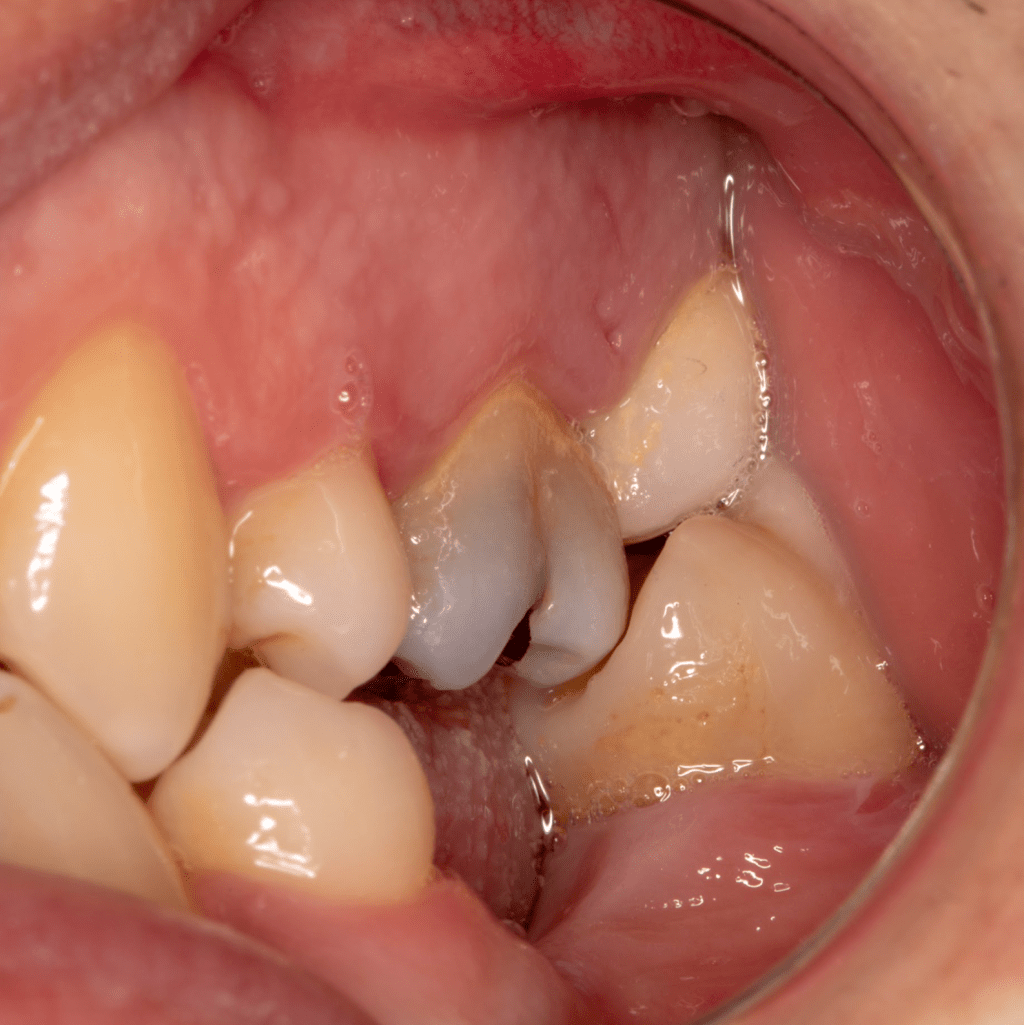

Vertical root fracture